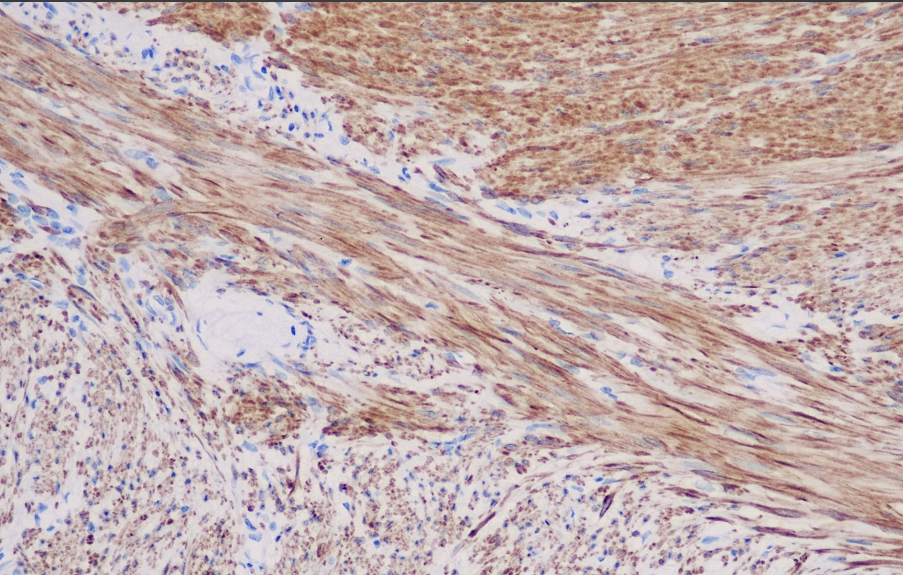

Cellular localization: cytoplasmic

Smoothelin is a component of the smooth muscle cytoskeleton protein and is only present in fully differentiated smooth muscle cells. Smooth muscle-like cells such as myoblasts, myoepithelial cells, skeletal muscle cells, and cardiac muscle cells do not contain Smoothelin. Due to this characteristic, the Smoothelin antibody is expressed in the muscularis propria of the bladder but not expressed or only weakly expressed in the mucosal smooth muscle, which is of significant importance for the staging of bladder cancer. The Smoothelin antibody plays a role in studies of tumors derived from smooth muscle cells. Immunohistochemical staining is positive in differentiated mature smooth muscle tumors, while poorly differentiated malignant smooth muscle tumors or smooth muscle-like tumors may be negative.

Smoothelin antibody reagents can specifically bind to Smoothelin molecular antigens. Immunohistochemistry kits containing Smoothelin antibody reagents are suitable for the auxiliary diagnosis of tumors derived from mature smooth muscle cells (such as vascular smooth muscle tumors and gastrointestinal smooth muscle tumors).